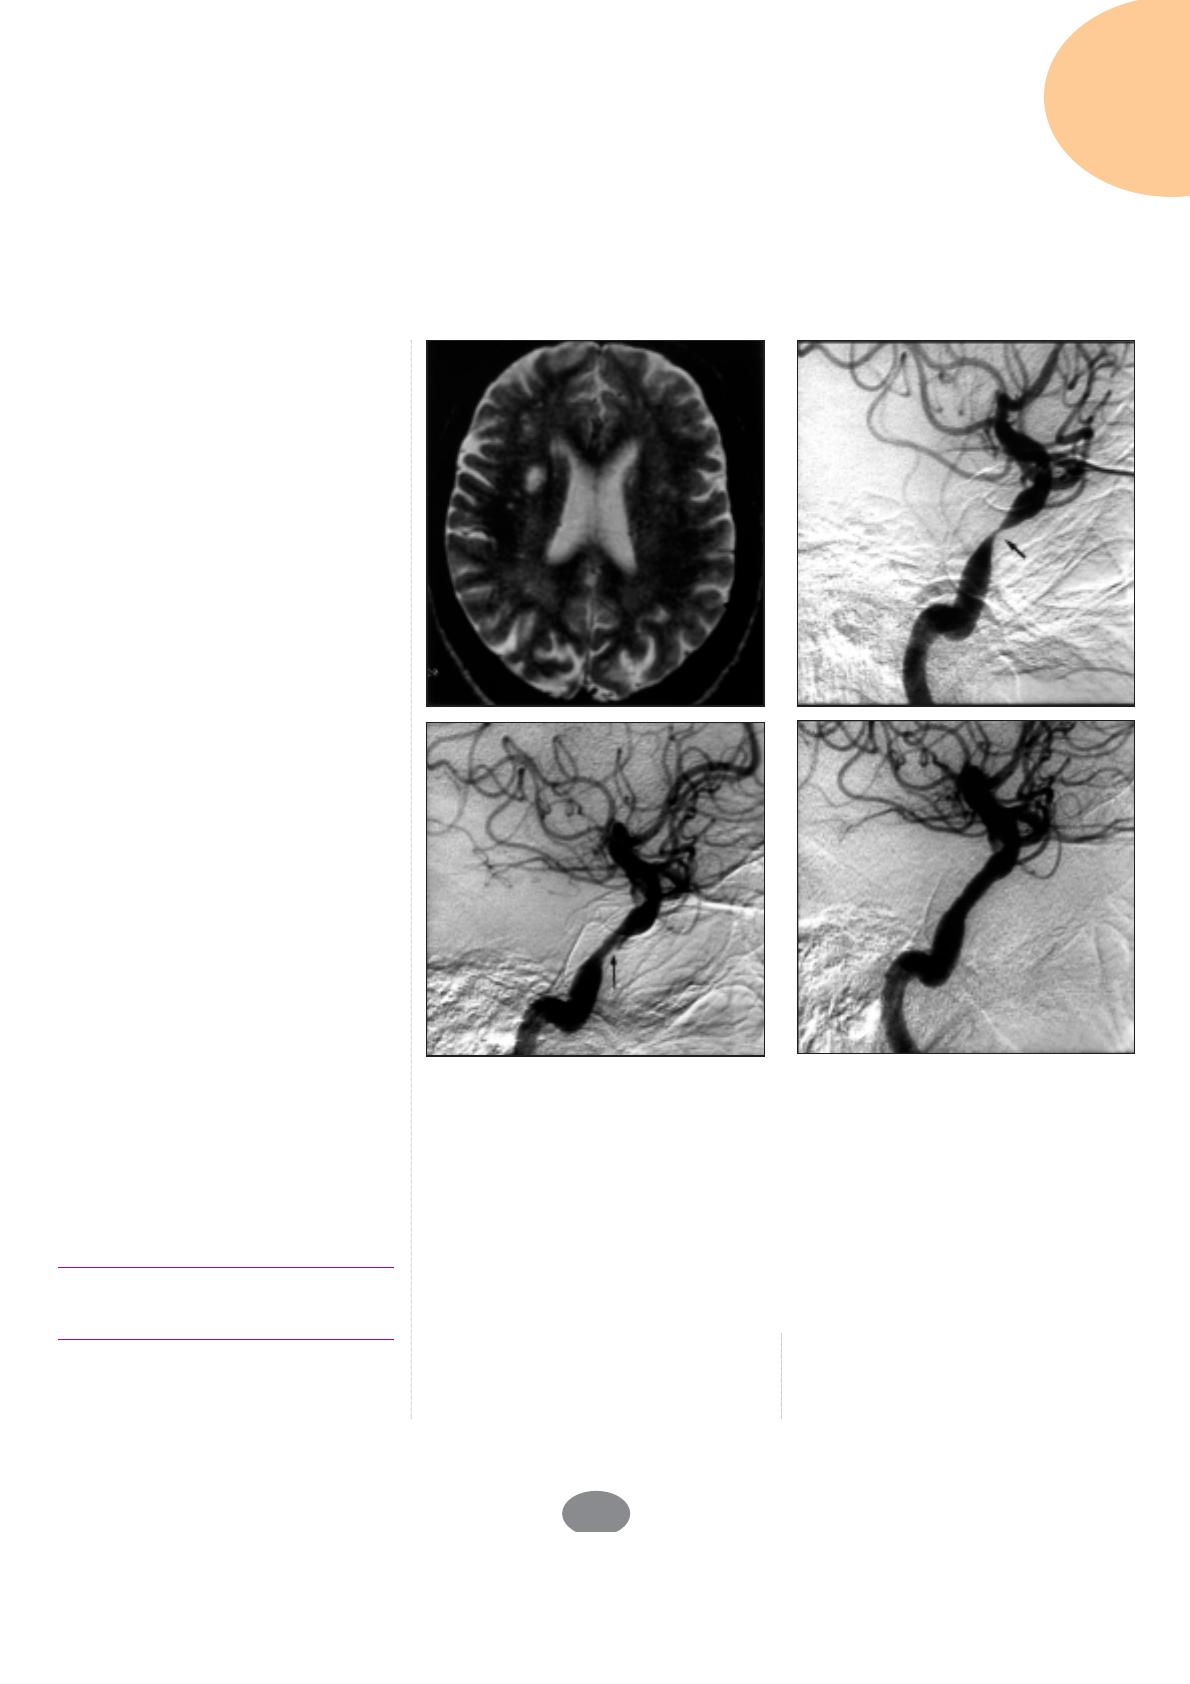

Figure 2. Angioplastie d’une sténose ostiale de l’artère vertébrale gauche.

Patient de 45 ans ayant présenté plusieurs accidents ischémiques thalamiques. Le dop-

pler cervical retrouve une thrombose de l’artère vertébrale droite.

A : L’artériographie sous-clavière gauche montre une sténose très serrée de l’origine de

l’artère vertébrale gauche (flèche).

B : Résultat angiographique après angioplastie et implantation d’un stent.

Figure 3. Angioplastie d’une sténose du TABC. Patiente de 60 ans ayant présenté des

épisodes récidivants de vertiges rotatoires. Les mesures de pression artérielle aux bras

ont montré une baisse de la pression systolique de 50 mmHg au bras droit.

A : L’aortographie retrouve une sténose serrée de l’origine du TABC (flèche).

B : Résultat après angioplastie-stenting de la sténose.